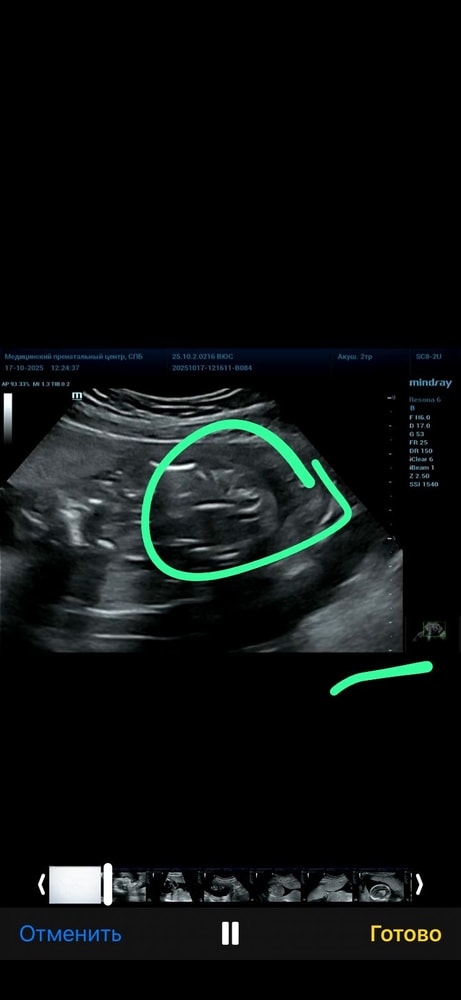

хочу выслать фото с узи, конечно понимаю что не все поймут узи, но вдруг у кого-то было похожее.